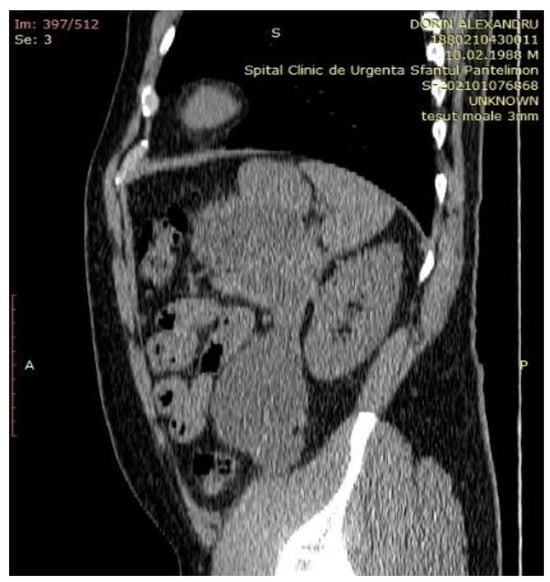

Case Presentation

- Imaging